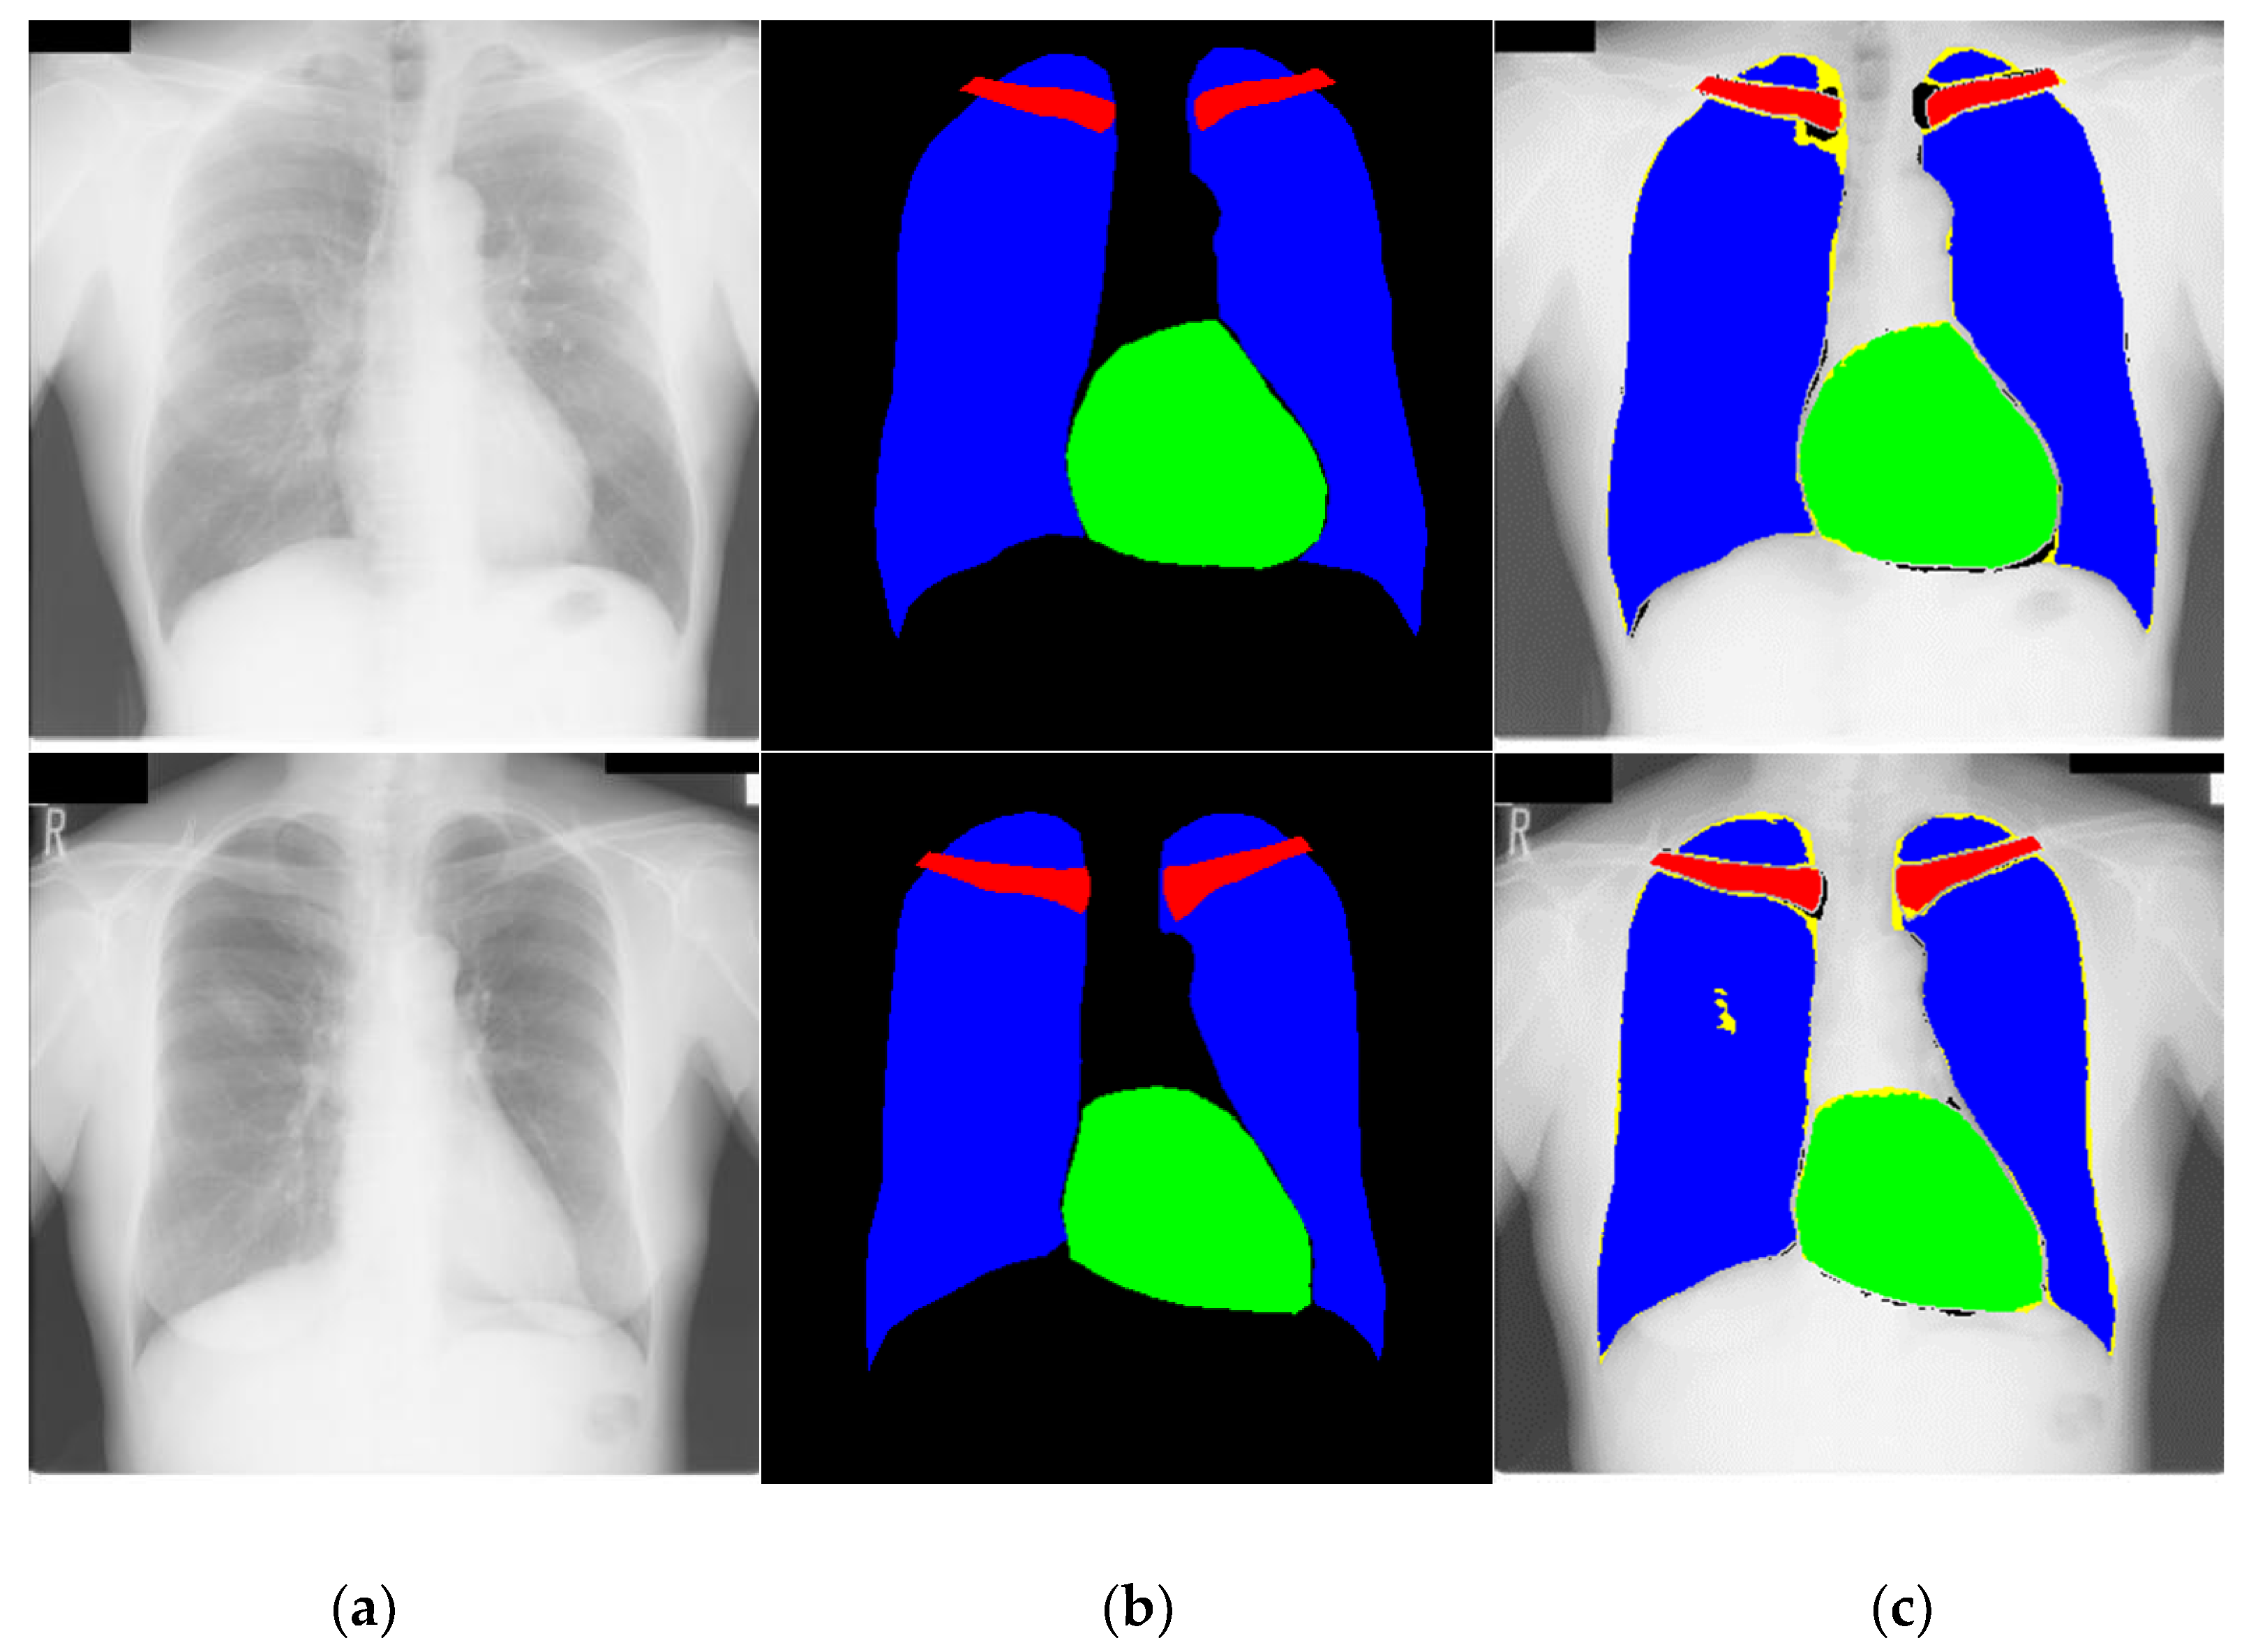

4.3.1. Chest Anatomy Segmentation Testing Using CardioNet